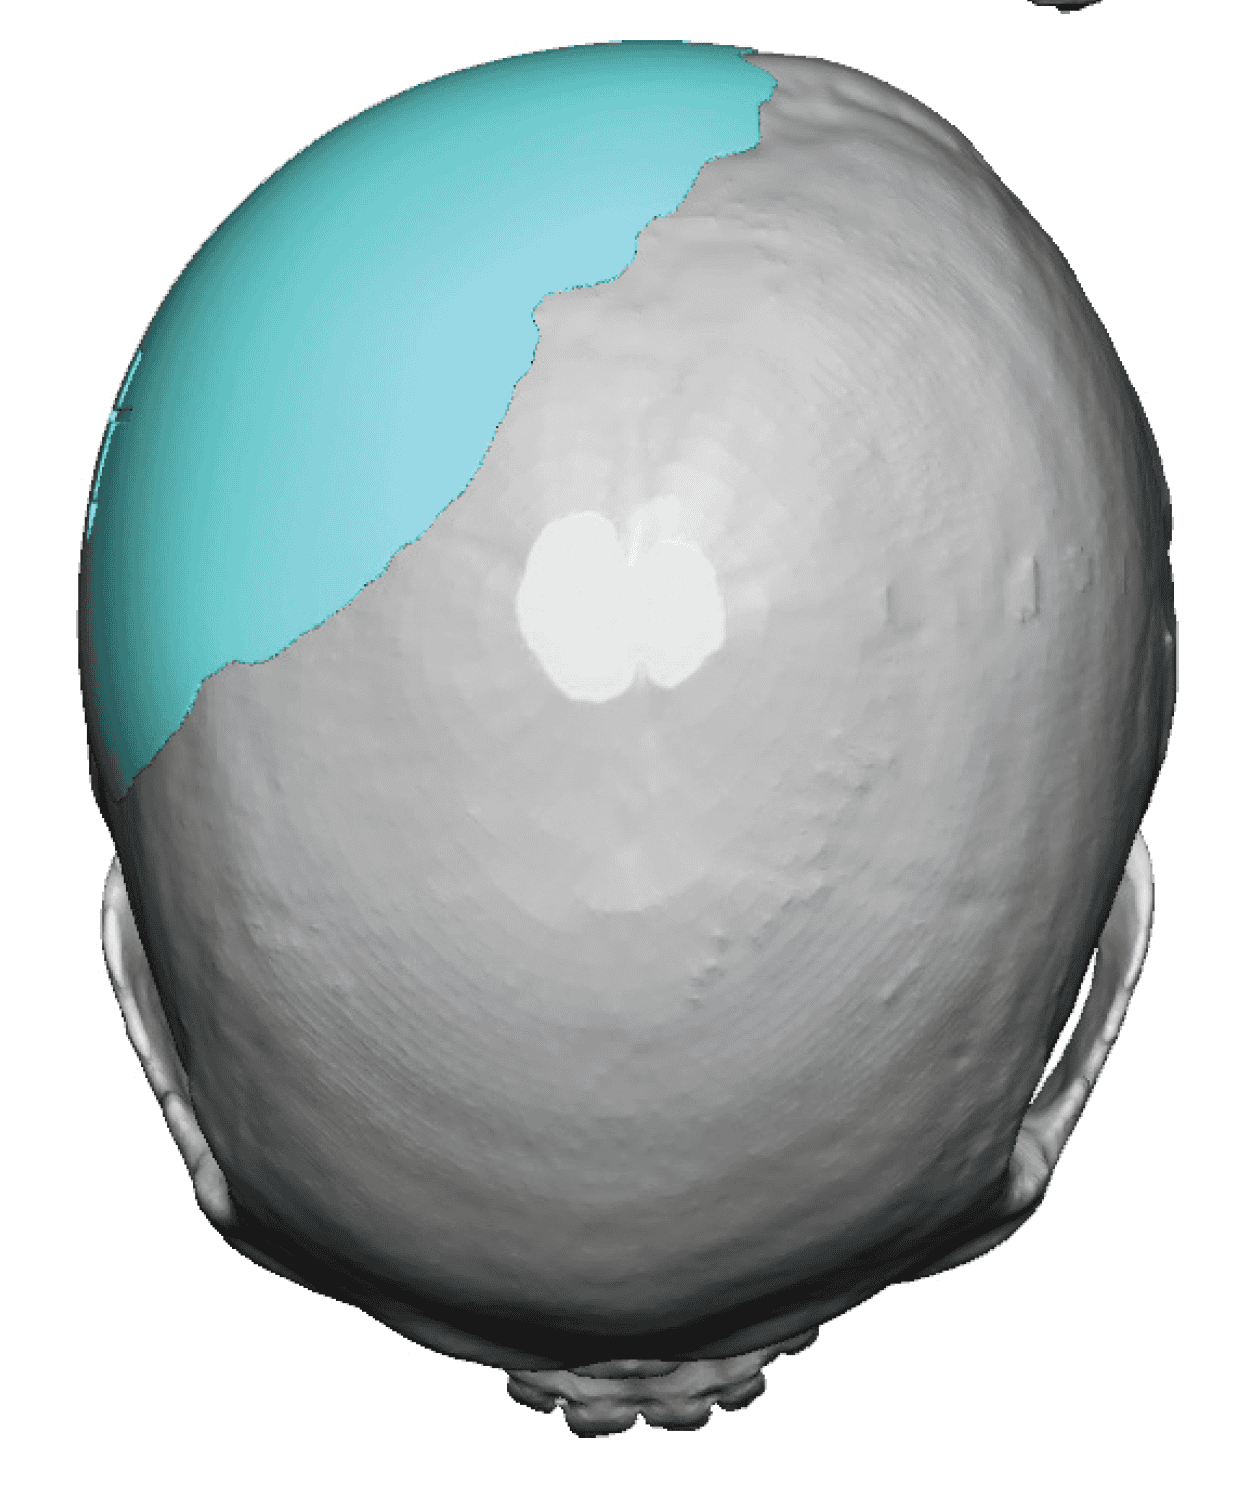

Desire for change of head shape from front view form an inverted V shape to a rounder and wider head shape.

Placement of custom extended forehead-temporal implants through incisions in the crease behind the ear. (he had a prior back of head skull implant which is green in the implant designs and which the head widening implants partially covered it)

Desire for change of head shape from front view form an inverted V shape to a rounder and wider head shape.

Placement of custom extended forehead-temporal implants through incisions in the crease behind the ear. (he had a prior back of head skull implant which is green in the implant designs and which the head widening implants partially covered it)